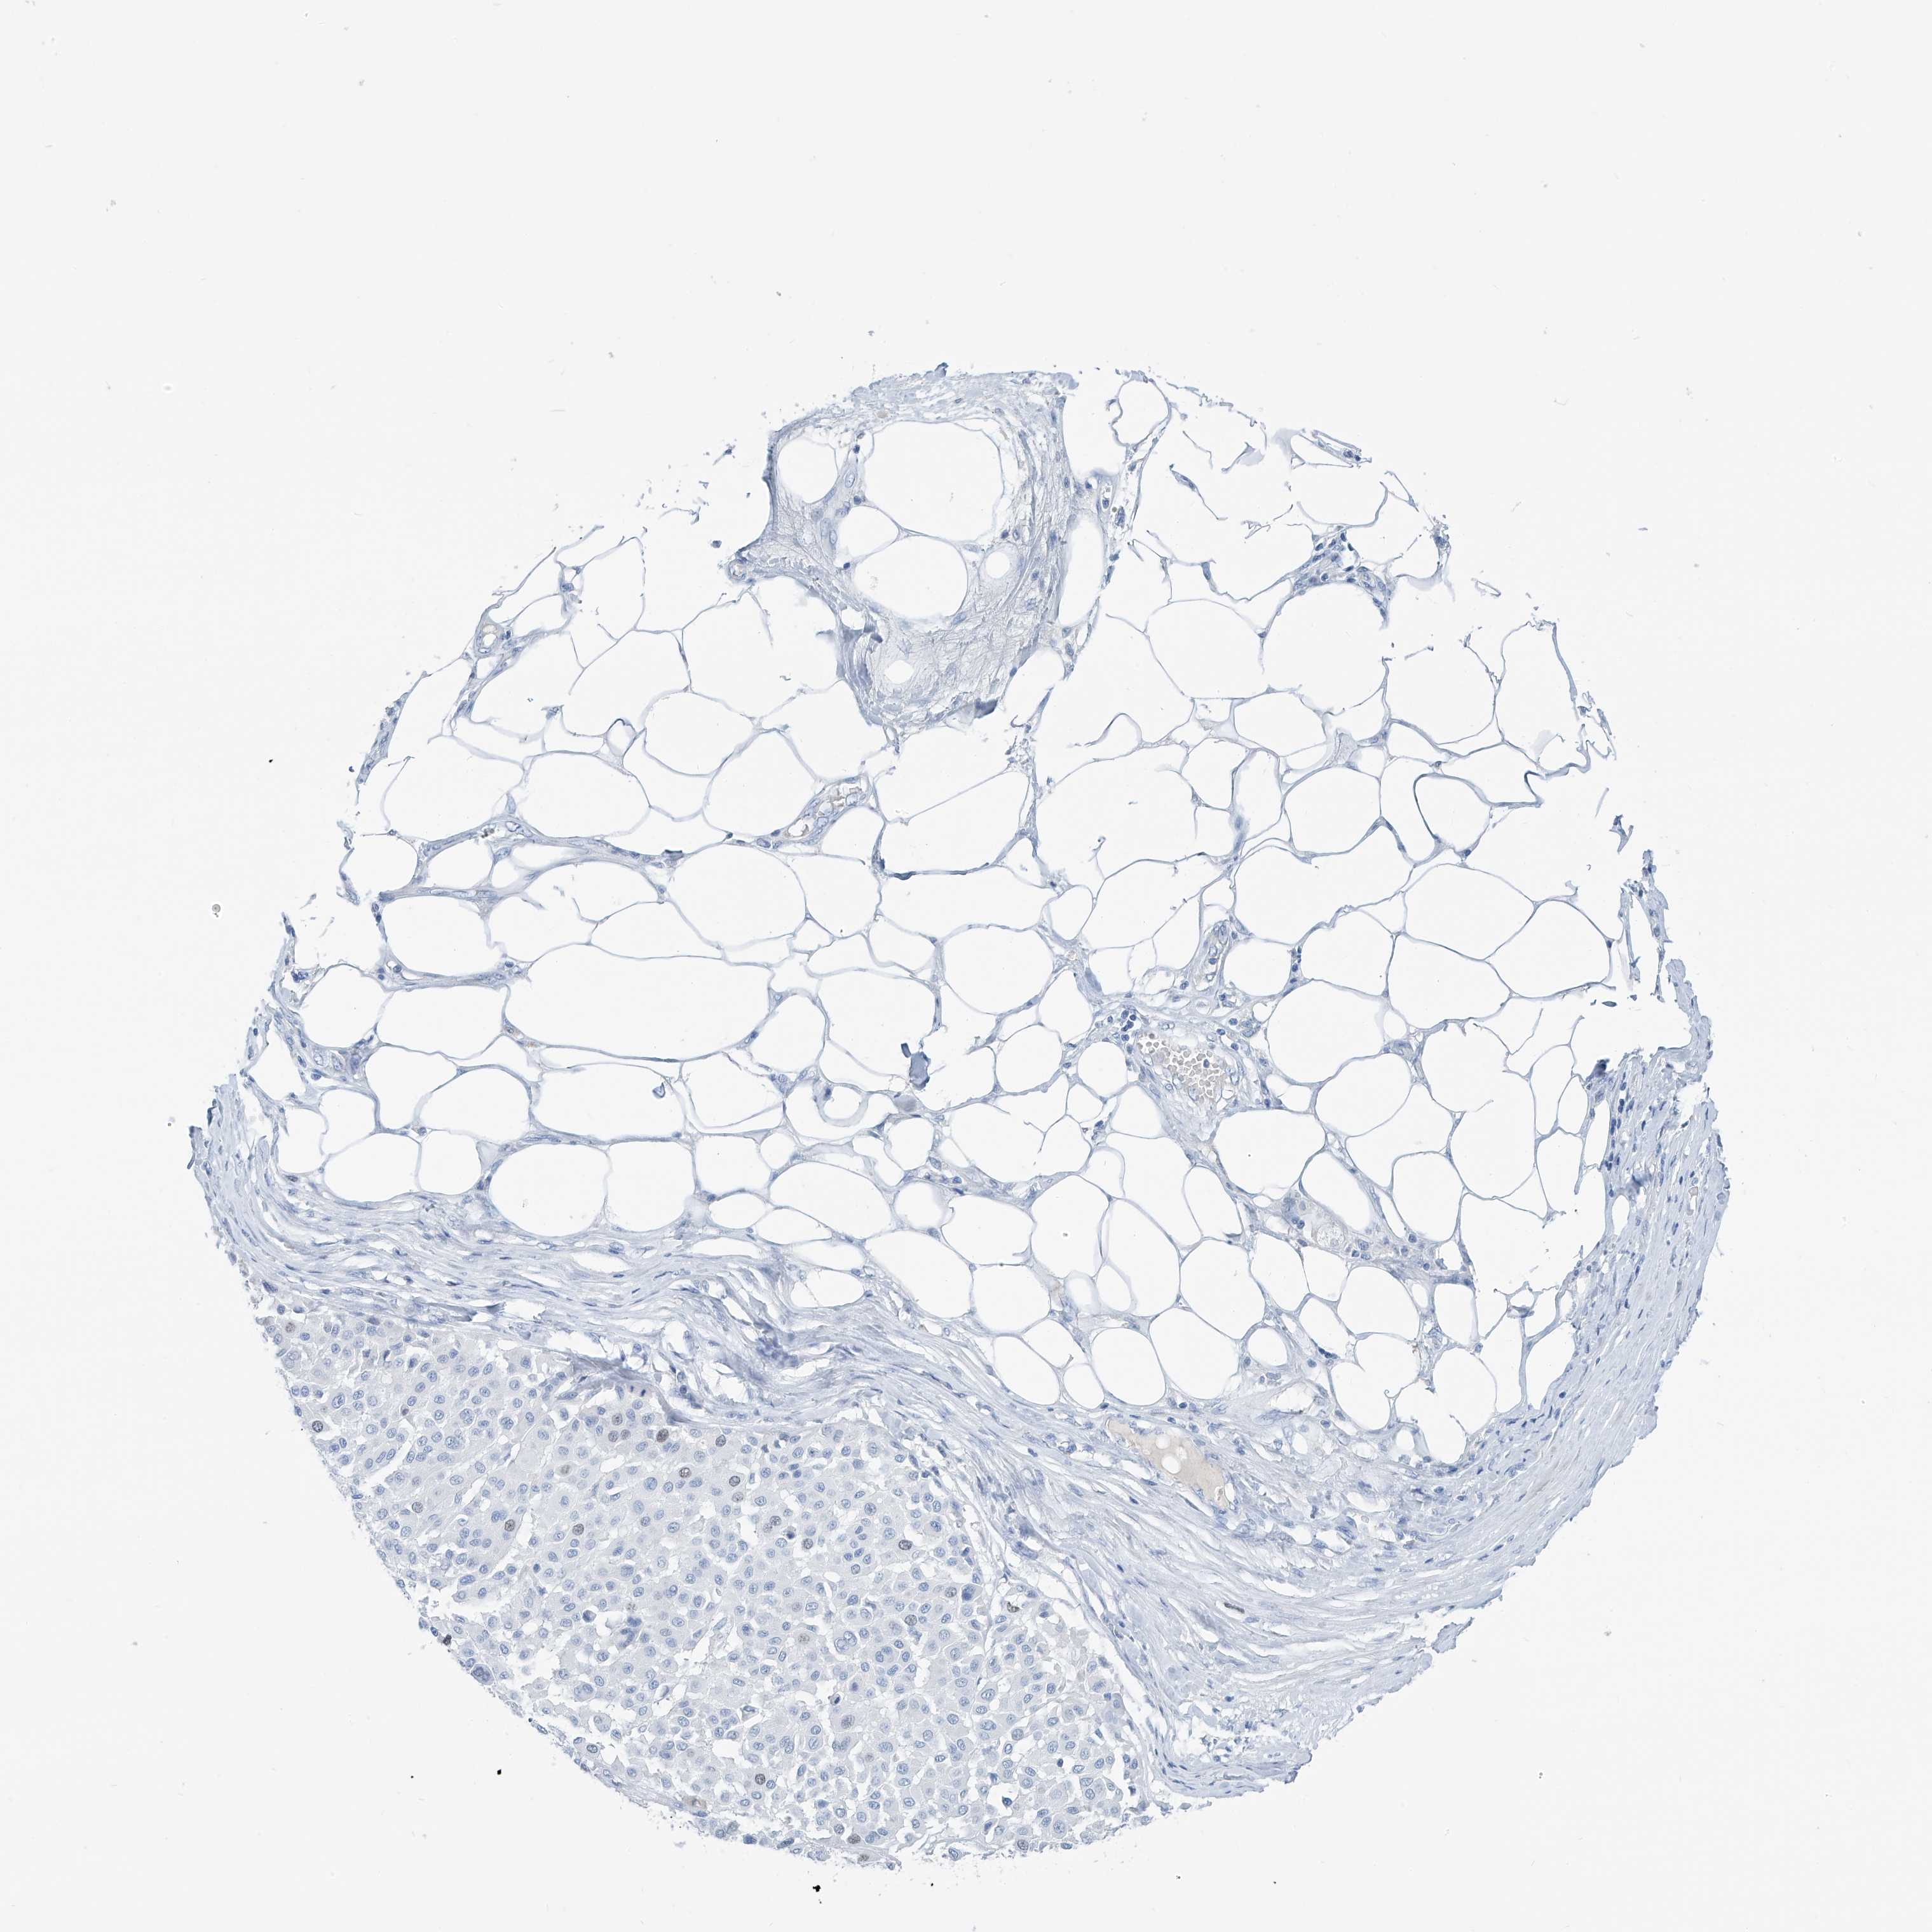

MELANOMA - Protein expressioni

A mouse-over function shows sample information and annotation data. Click on an image to view it in a full screen mode. Samples can be filtered based on level of antibody staining by selecting one or several of the following categories: high, medium, low and not detected. The assay and annotation is described here.

Note that samples used for immunohistochemistry by the Human Protein Atlas do not correspond to samples in the TCGA dataset.

Antibody stainingi

Antibody staining in the annotated cell types in the current human tissue is reported as not detected, low, medium, or high, based on conventional immunohistochemistry profiling in selected tissues. This score is based on the combination of the staining intensity and fraction of stained cells.

Each image is clickable and will lead to virtual microscopy that enables deeper exploration of all samples and also displays staining intensity scores, fraction scores and subcellular localization as well as patient and tissue information for each sample.

Antibody HPA035163

Staining

High

Medium

Low

Not detected

Intensity

Strong

Moderate

Weak

Negative

Quantity

>75%

75%-25%

<25%

None

Location

Nuclear

Cytoplasmic/membranous

Cytoplasmic/membranous,nuclear

Malignant melanoma, NOS

Malignant melanoma, Metastatic site